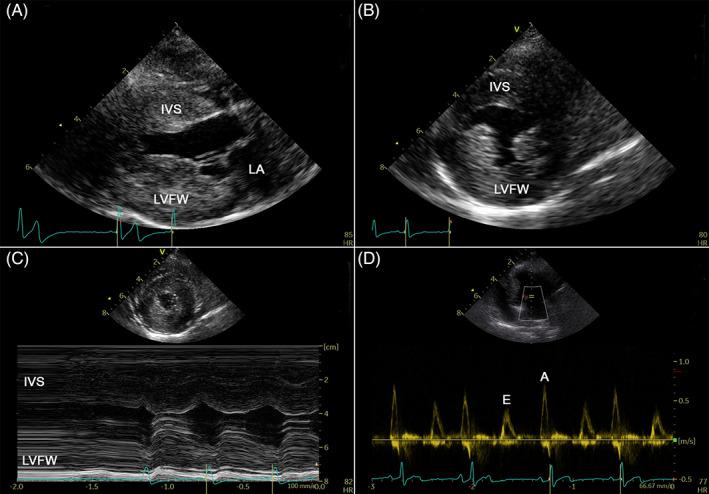

Three hundred and forty-five dogs with LV hypertrophy were identified, of which 277 were excluded. The remaining 68 dogs were 0.3 to 14 years old and predominantly <10 kg (85%), and without a sex predilection. Twenty-four % were Shih Tzu and 24% terrier breeds. Most (80%) had a systolic heart murmur. Owner-determined exercise intolerance (37%) and syncope (18%) were most commonly reported signs. The majority (84%) of dogs had symmetrical LV hypertrophy, whereas asymmetrical septal and LV free wall hypertrophy was observed in 9% and 6% of dogs, respectively. Isolated basal interventricular septal hypertrophy was not observed. Commonly recorded were systolic anterior motion of the mitral valve (60%) and LV diastolic dysfunction (89% of dogs where diastolic function was evaluated). Six dogs died unexpectedly, and 3 developed congestive heart failure. Known survival times were between 1 day and 114 months after diagnosis.